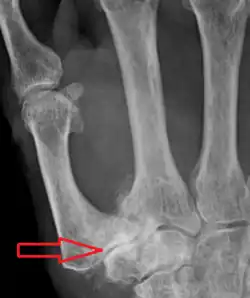

Diagnosis

TMC OA is diagnosed based on symptoms and signs.[8] Radiographs can confirm the diagnosis and the severity of TMC OA. Other diagnoses in this region include scaphotrapezial trapezoid arthritis and first dorsal compartment tendinopathy (De Quervain syndrome) although these are usually easy to distinguish.

Classification

TMC OA severity was classified by Eaton and Littler which can be simplified as follows:[21][22]

Stage 1:

- slight widening of the joint space

- < 1/3 subluxation of the joint (in any projection)

Stage 2:

- Osteophytes, < 2 mm in diameter, are present. (usually adjacent to the volar or dorsal facets of the trapezium)

Stage 3:

- Osteophytes, > 2 mm in diameter, are present (usually adjacent to the volar and dorsal facets of the trapezium)

- Slight joint space narrowing

Stage 4:

- Narrow joint space

- Concomitant scaphotrapezial arthritis

A simpler classification is no arthritis, some arthritis, and severe arthritis.[23] This simpler classification system omits the potentially contradictory details of the Eaton/Littler classification and keeps scaphotrapezial arthrosis separate.